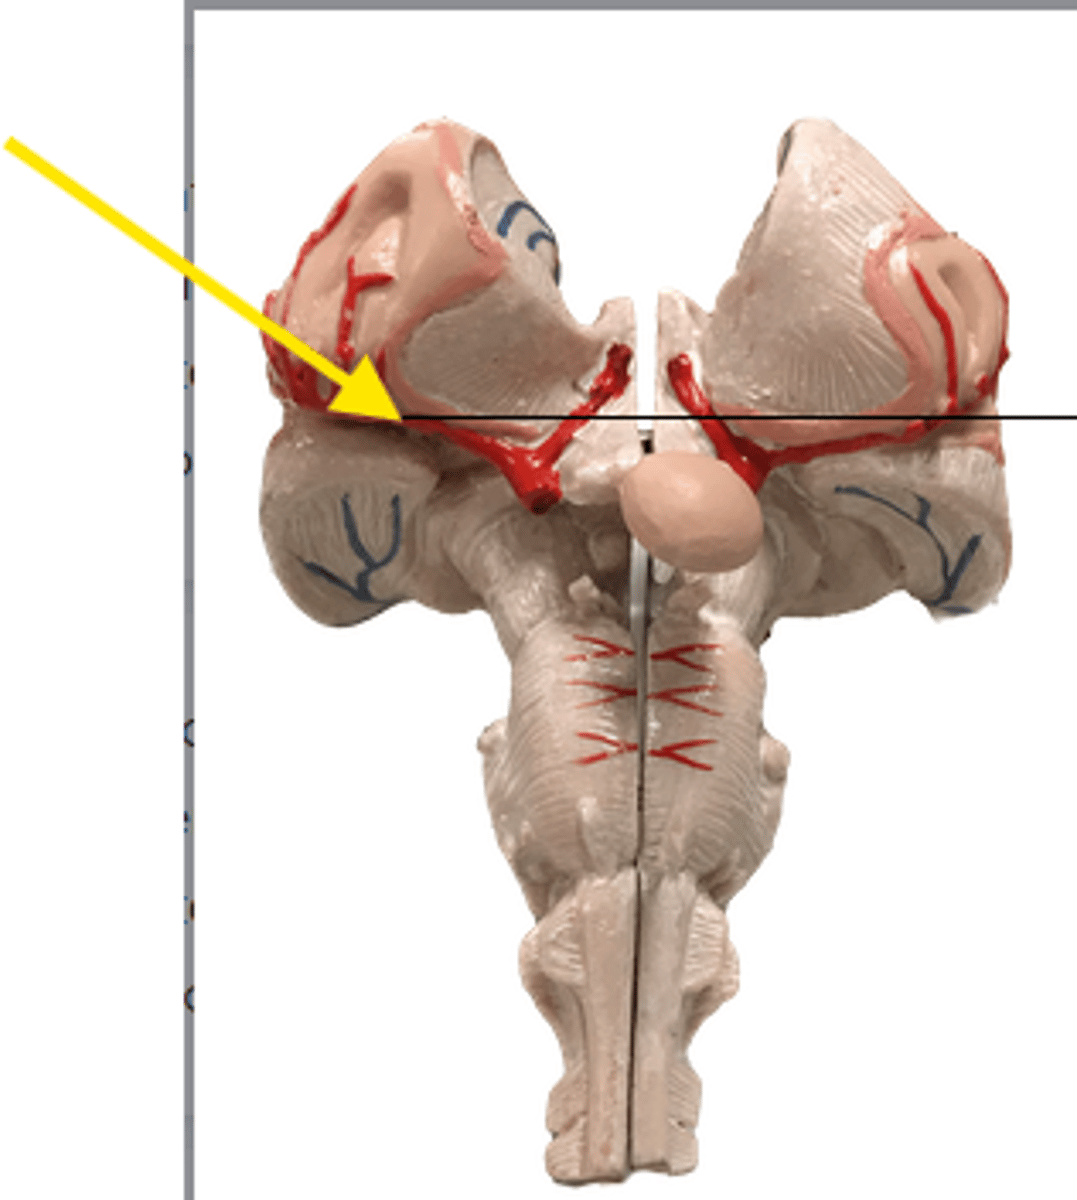

What part is the yellow arrow pointing to?

what is the yellow arrow pointing at?